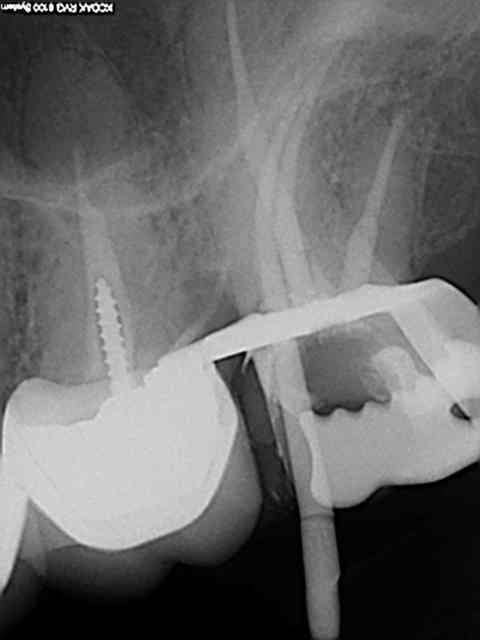

Exemple concret, de ce samedi (exceptionnellement au boulot car c'est un pote qui travaille sur Paris et qui a une semaine de vacances), j'en ai tous les jours.

la première radio date de 2011 issue d'un status inutile selon la sécu. Suspicion de reprise en mésial sous l'onlay de 27, noté sur le dossier à surveiller. Le patient appelle pour douleurs lancinantes spontanées la semaine dernière en haut au fond et à gauche exacerbées par le froid.

Diagnostic clair net et précis et par téléphone en plus : ca n'est pas du au tt merdique de la 26. Ce qui est confirmé in situ par la radio numéro 2 prise le jour meme de l'endo.

Comme à mon habitude je m'excuse d'avoir irradié le patient copieusement ( à raison de 70 kv et 0,099 s par cliché) plutot qu'un seul cliché argentique en fin de tt ( 70 kv aussi mais 1,3 s d'exposition lui) développé en fin de journée comme ca a du etre le cas pour le tt de 26 ( et m... encore raté).

Je sais pas moi mais le résultat parle de lui meme ( putain de mv2 que j'ai réussi à choper dans un 2 eme temps une fois les autres obturés)

Taille empreinte provisoire dans la foulée , l'avantage de la gutta chaude.

Vous préférez quoi dans votre bouche ? une seule radio et un tt endo comme la 26 ou 6 clichés et mon tt endo de 27 ?